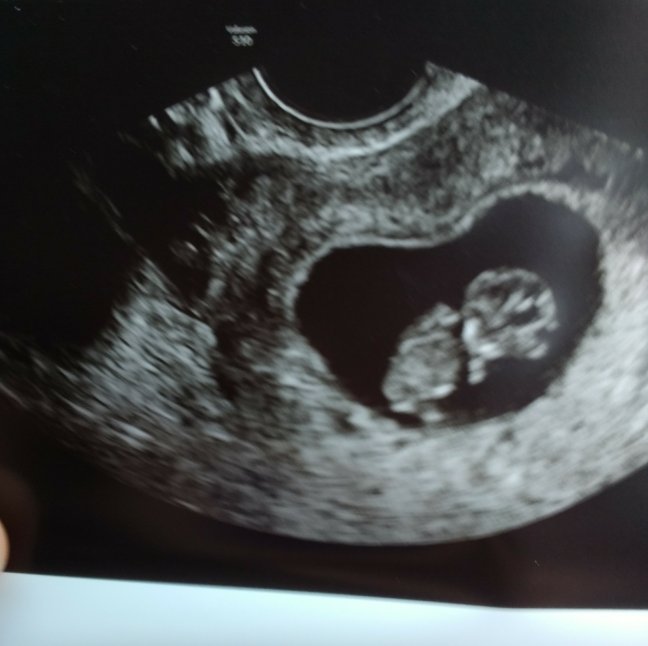

Today was good. Saw a good friend, the kids played, she brought me cupcakes, complimented me on my freshly acquired motherly figure (and I hers, because our due dates are like 5 days apart 🤣) y'all, everybody needs a friend like that. She refreshes my soul, and I hope I do the same for her. … Continue reading How Deep the Father’s Love